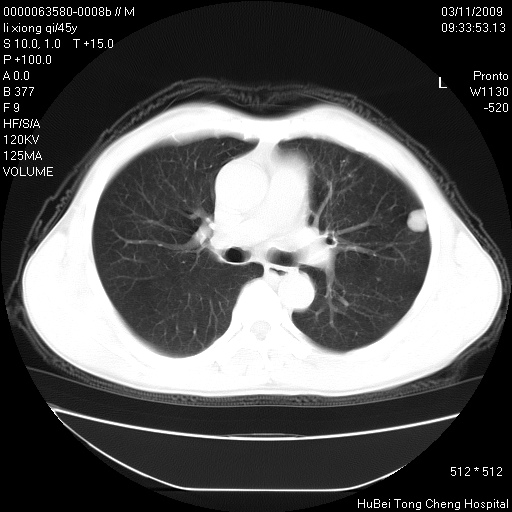

患者 男,45岁。胸痛,咳嗽伴痰中带血1月余。

临床诊断:肺结核?

胸部ct轴位平扫(层厚10mm,螺距1.5,重建间隔10mm),图像如下:

考虑肝癌肺转移

考虑肝癌肺转移。

肝癌肺转移